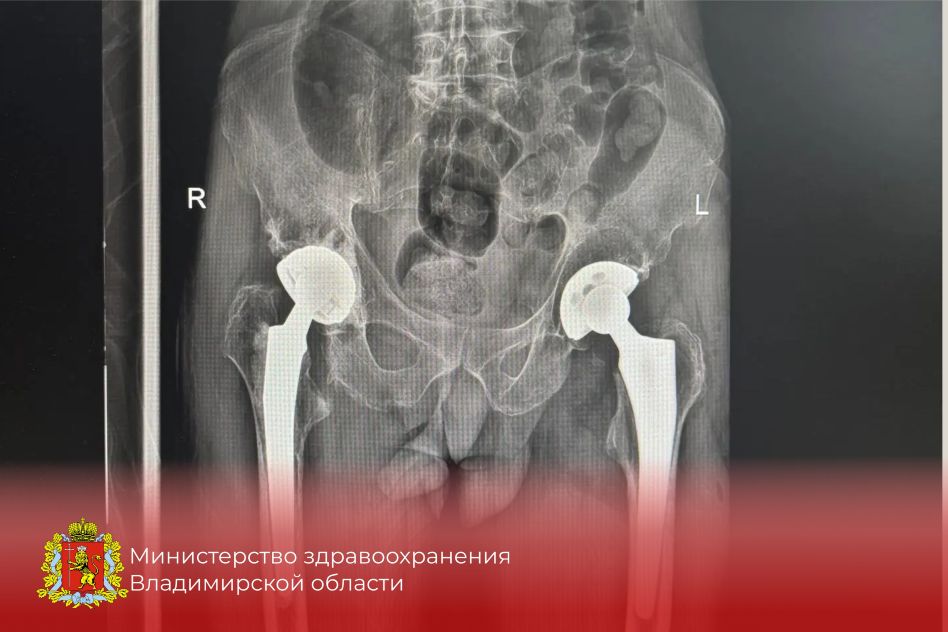

Оптимистичная информация пришла из областного министерства здравоохранения. Оказывается, за этот год в травматологическом отделении Центральной городской больницы Коврова хирурги установили более десяти эндопротезов тазобедренного сустава.

Сообщается, что это передовой метод лечения переломов тазобедренного сустава — той самой шейки бедра. И его ковровские врачи успешно освоили. Эта современная методика эндопротезирования позволяет, в частности, встать на ноги пожилым людям, которые сломали проксимальный отдел бедренной кости. А получить такой перелом человек за 60 может, даже упав с высоты собственного роста.

По мнению областного минздрава, можно уверенно говорить о том, что новая технология успешно внедрена в практику ковровской ЦГБ. «Перспективы развития этого направления в районной медицине выглядят обнадеживающе. Эндопротезирование тазобедренного сустава при переломах шейки бедра становится всё более доступным для пациентов».